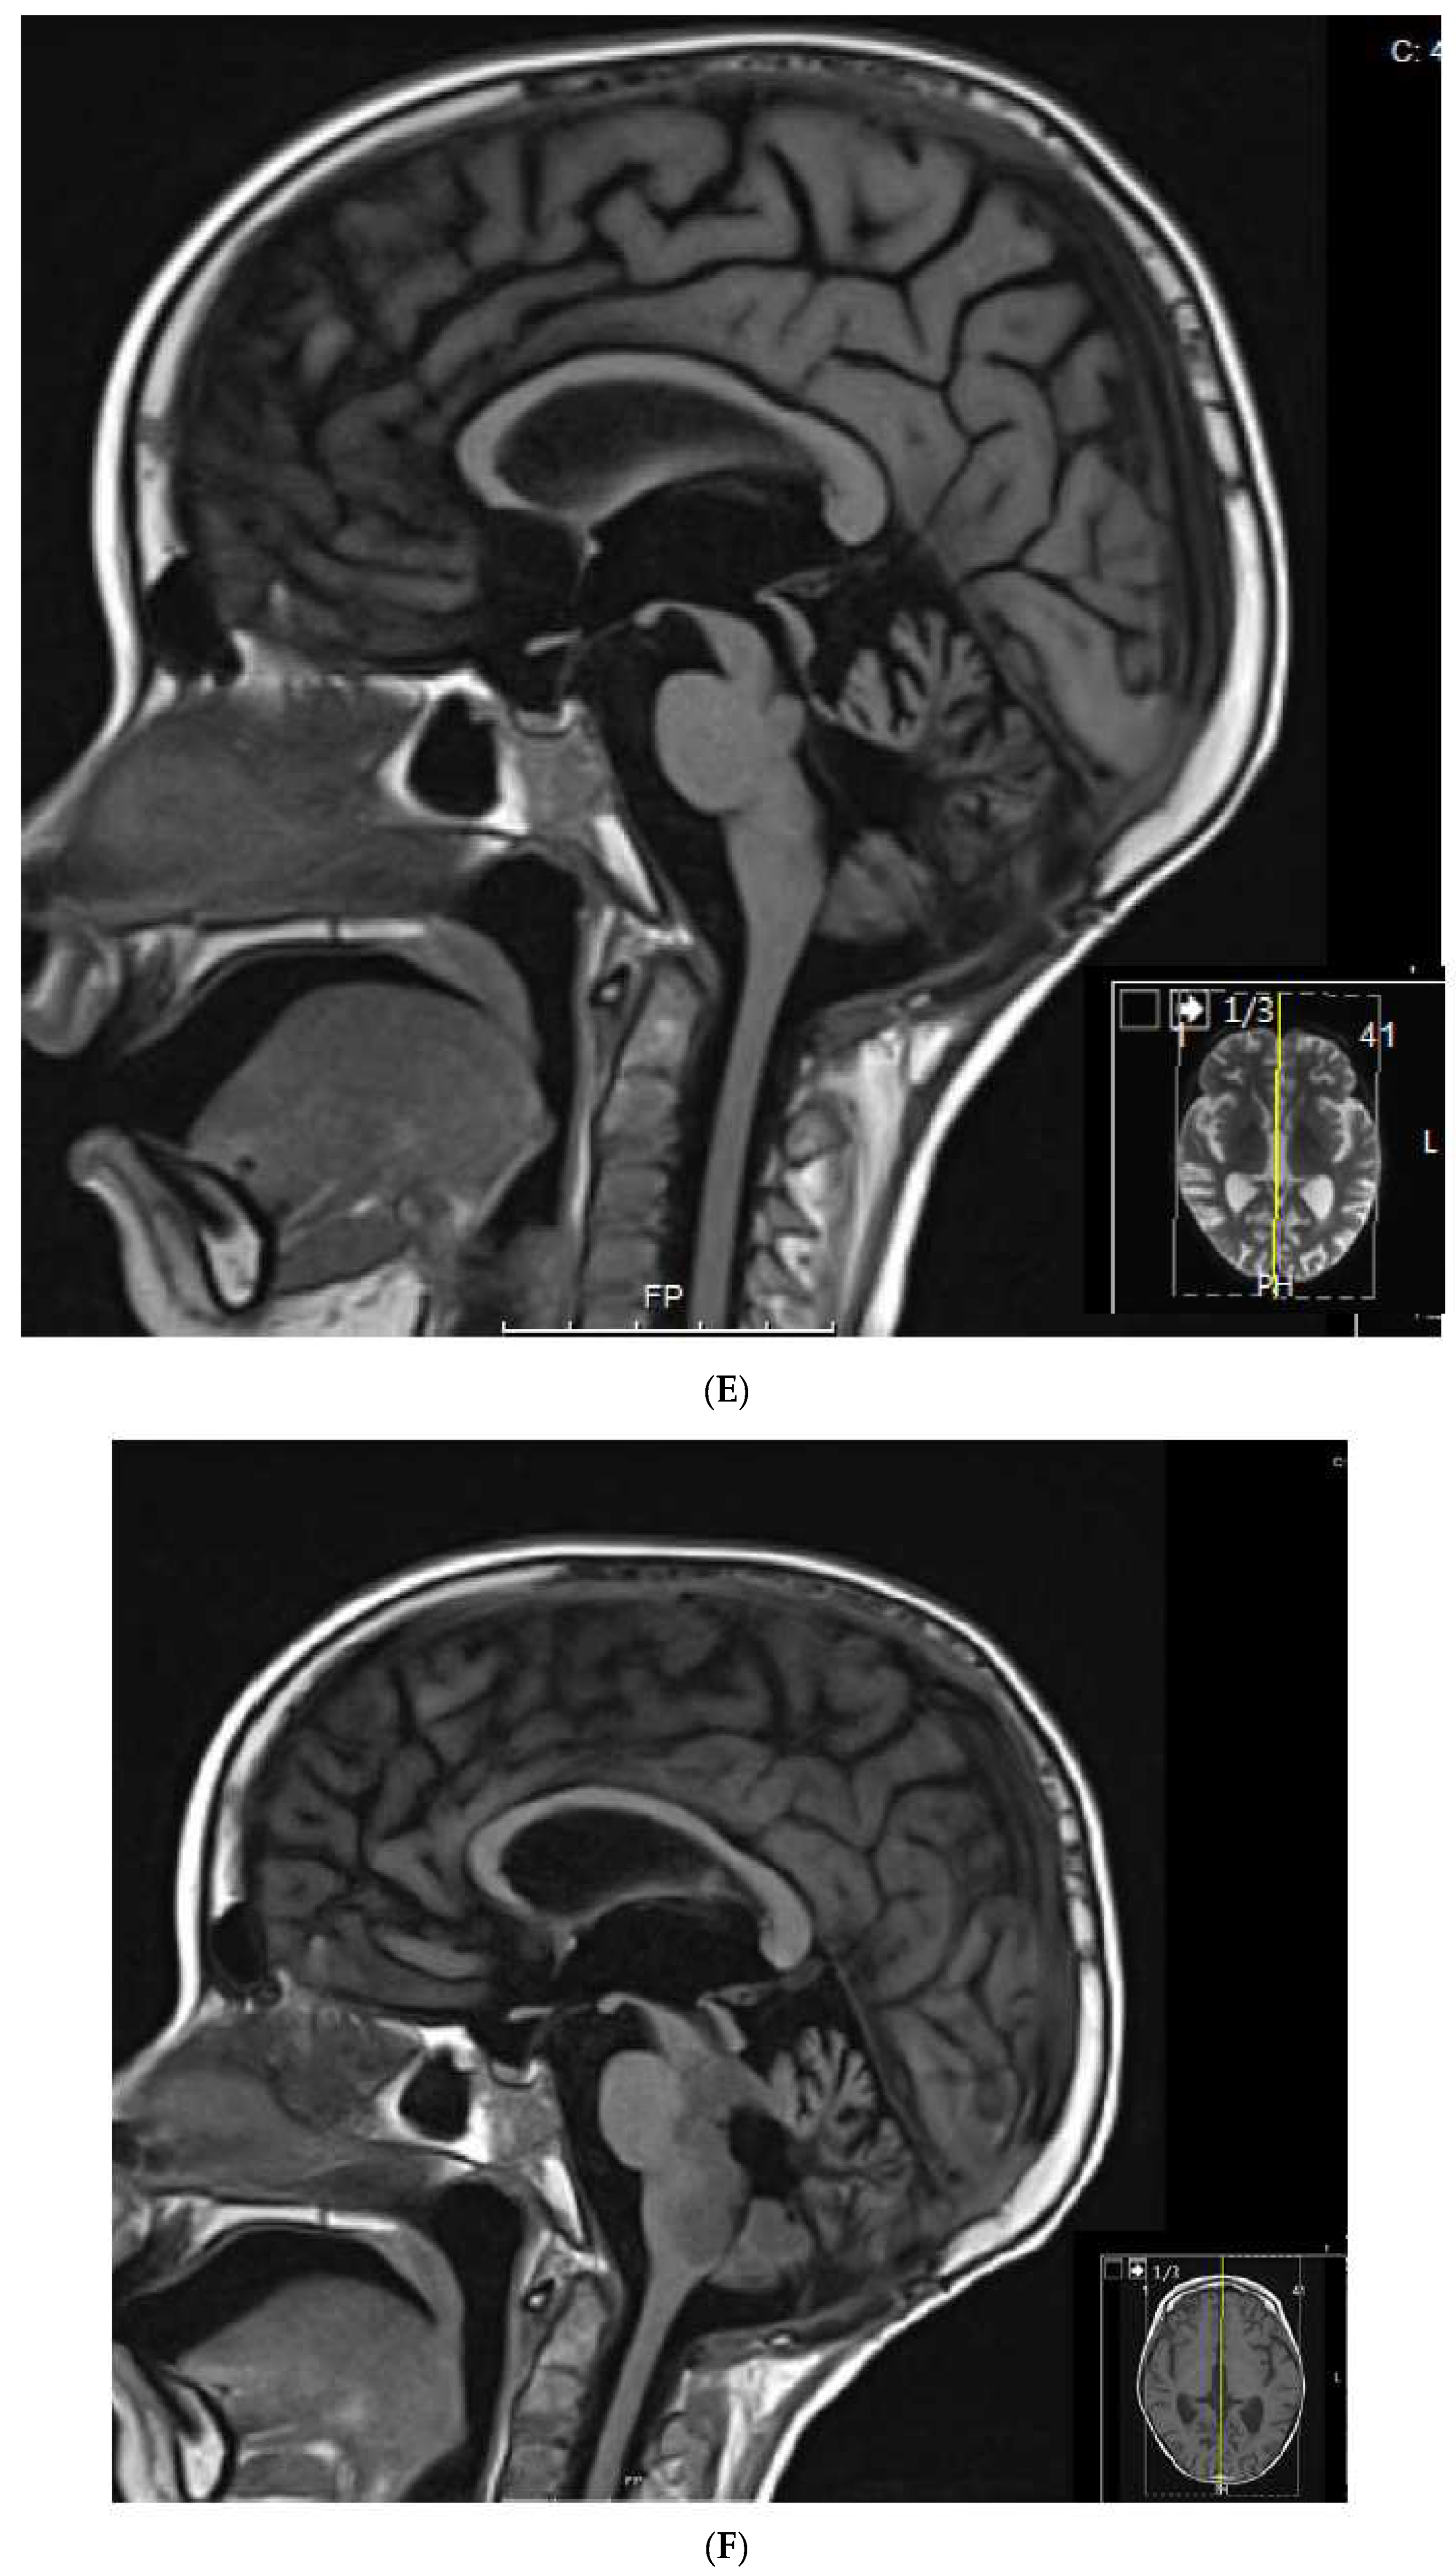

Collectively, these observations have led us to propose a study that incorporates tyrosine kinase inhibitors (TKI) to metronomic chemotherapy. Our backbone of choice to compare with TKI is celecoxib-valproic acid based on our experience and the growing interest in anti-histone drugs that have undergone trials with responses in difficult pediatric tumors [47]. All patients will receive alternating cyclophosphamide and etoposide as described in this report. This study depicted in Figure 5 will involve screening refractory patient’s tumors for metabolic targets, and treating the patients with alternating etoposide-cyclophosphamide and either continuous celecoxib-valproic acid or continuous TKI if a targetable aberrant metabolic pathway is identified.

Figure 5.

Schematic of future planned studies for pediatric cases eligible for metronomic chemotherapy. Proteomic and metabolic pathway analysis, where feasible, will be used to determine eligibility of patients to receive specific tyrosine kinase inhibitor (TKI) therapy coupled with metronomic chemotherapy, which involves alternating cycles of metronomic etoposide with metronomic cyclophosphamide. Patients not selected or not eligible for TKI-based therapies will receive valproic acid (VA) and celecoxib with metronomic chemotherapy as outlined in this manuscript.